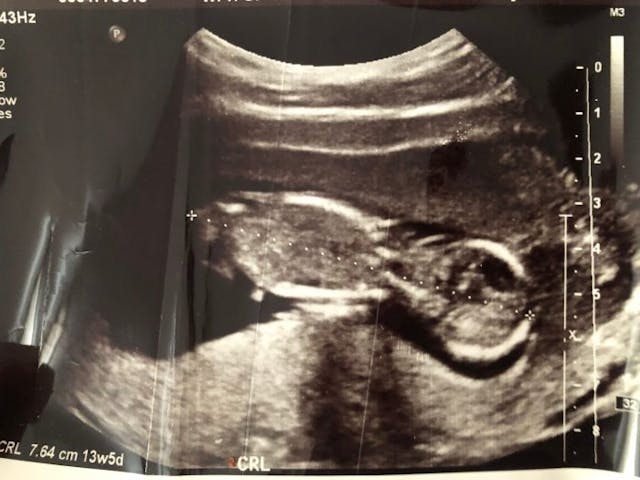

In 2019, Sarah and Reed were thrilled to be expecting their second child, but their world was shaken when the unexpected happened. At 13.5 weeks, Sarah experienced a subchorionic hemorrhage, bleeding under one of the membranes that surrounded her preborn baby. Doctors at the emergency room sent her home on bed rest, but a week later, she began experiencing pain so strong that she returned to the ER. This time, doctors removed two blood clots from her cervix.

An ultrasound showed that the baby was fine and that Sarah was not in preterm labor. Doctors sent her home again, but she was only there for a few minutes when she felt excruciating pain. Then her water broke.

Sadly, an ultrasound in the ER revealed that their nearly 15-week preborn baby was no longer in the uterus. Sarah was told to lay back and push. The doctor said the baby’s head was stuck, and used tools to remove the baby.